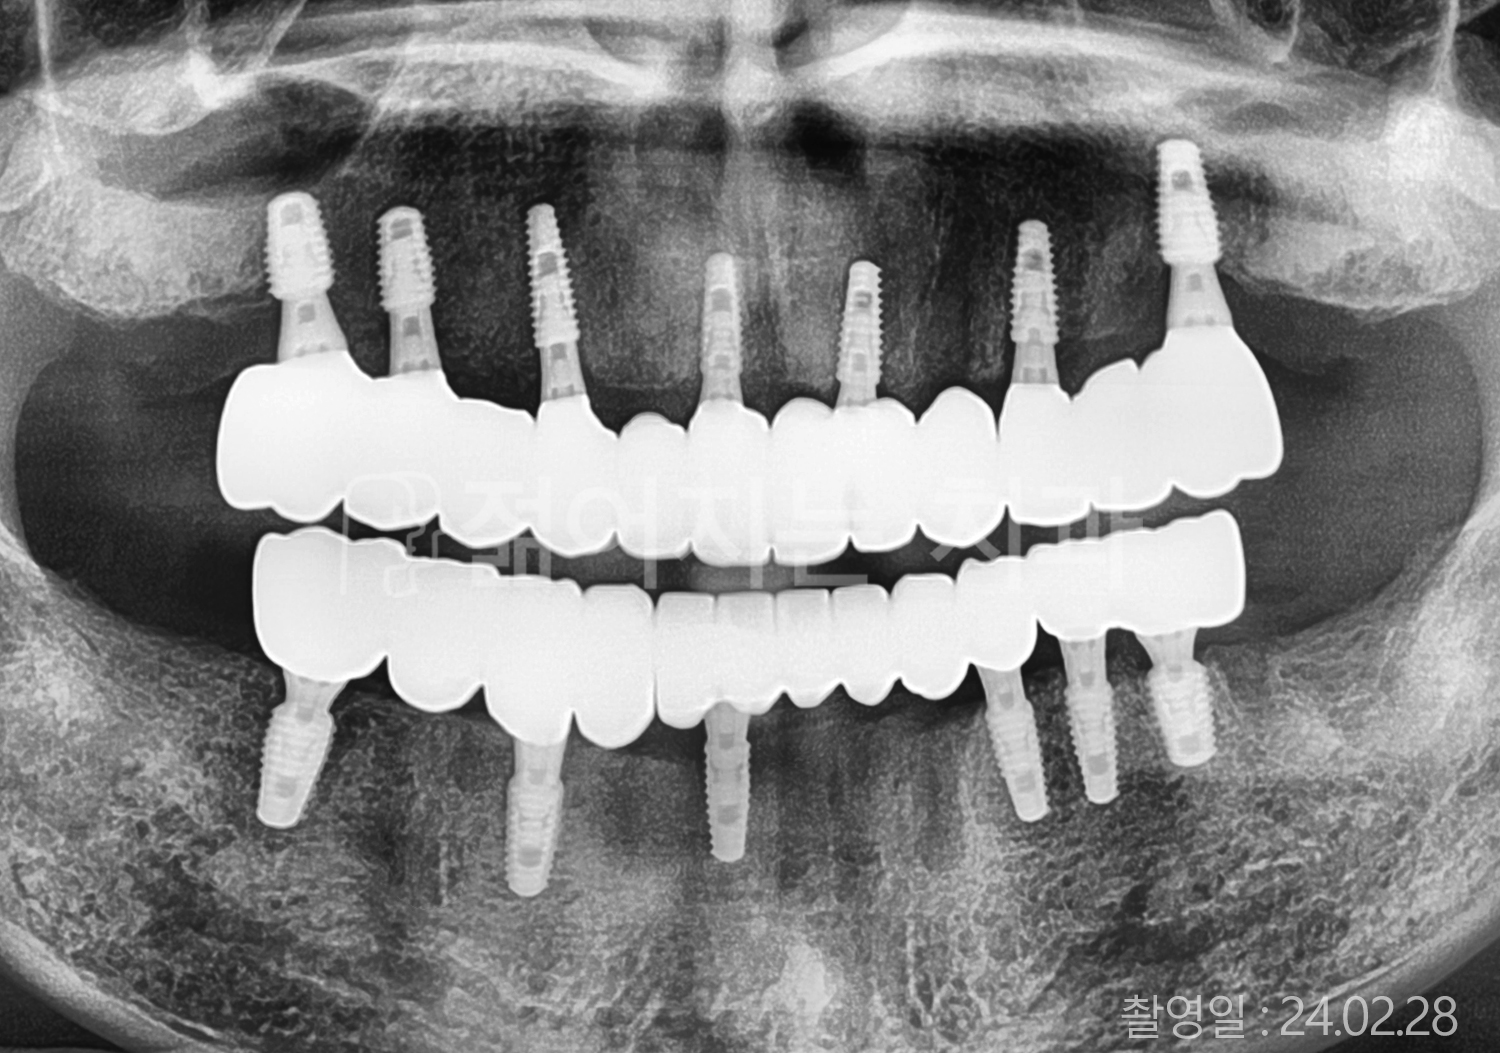

치료부위

식립개수

특이사항

• 60대 고혈압, 당뇨, 고지혈증 전체치아 10개 이상 임플란트